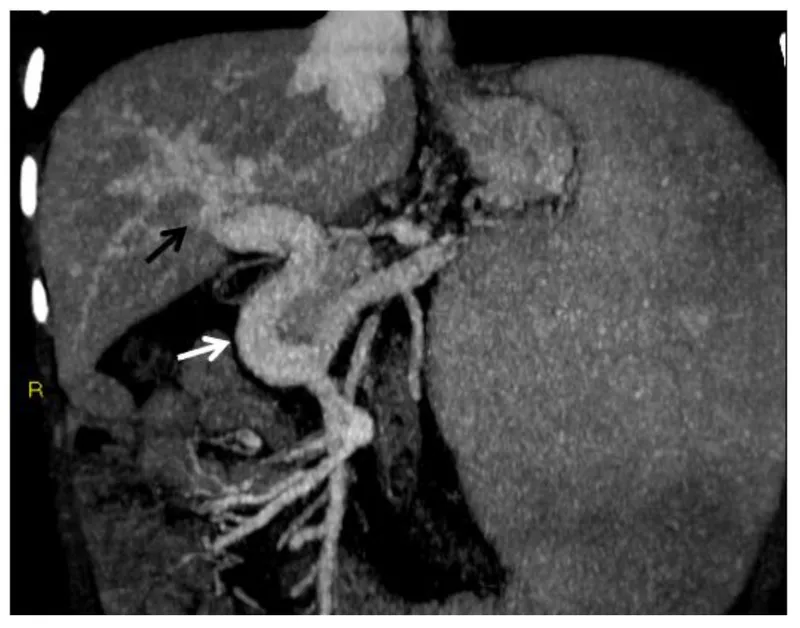

TIPS (Transjugular Intrahepatic Portosystemic Shunt): Key "pressure plunger".

- Mechanism: Creates a direct, low-resistance channel using a stent between the intrahepatic portal vein and a hepatic vein.

- Access: Transjugular (via internal jugular vein).

- Therapeutic Goal: Achieve portosystemic gradient (PSG) < 12 mmHg.

- Major Complications: Hepatic encephalopathy (HE) (up to 30%), shunt dysfunction (stenosis/occlusion).